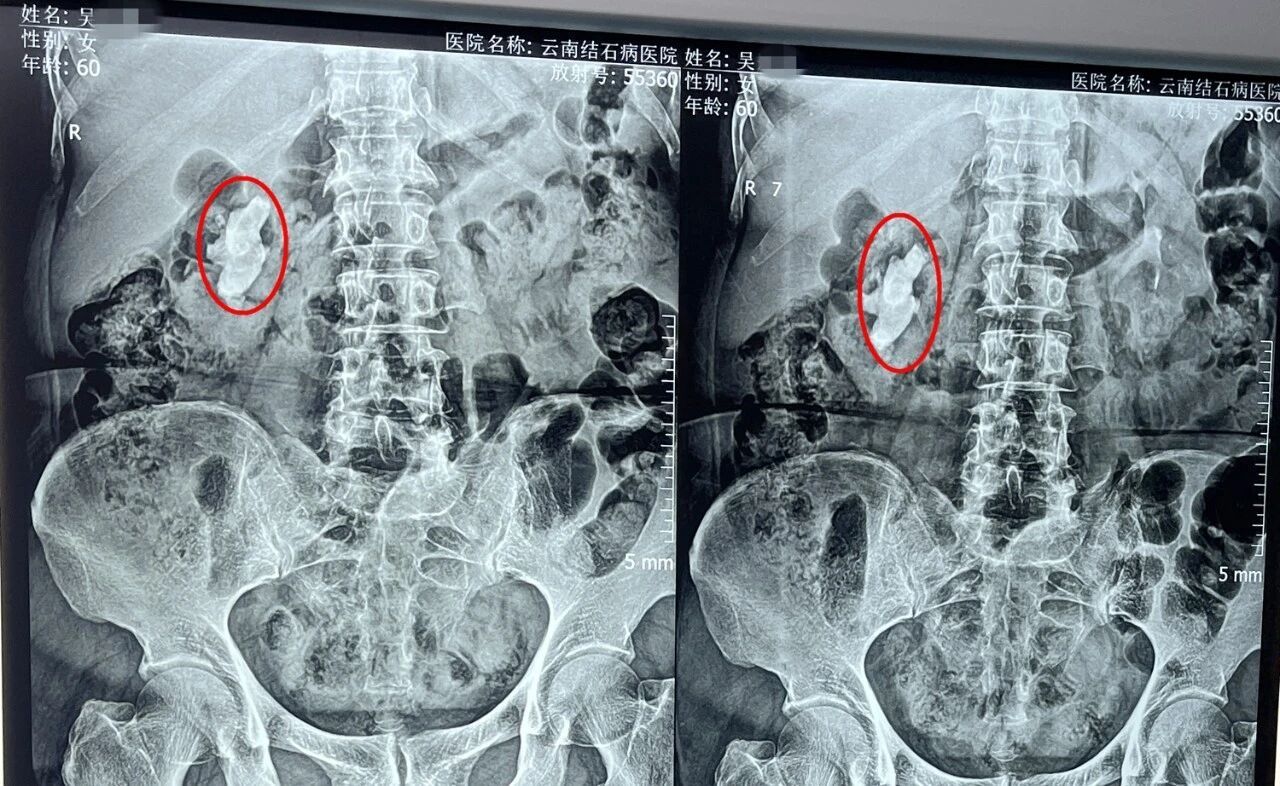

入院经过详细检查,泌尿外科黄鸿宾主任发现,吴女士的右肾上、中、下盏均遍布结石,其中最大一颗约3.6×2.7厘米,并且已经造成了右侧肾盂及部分肾盏的局限性积水。考虑到患者肾脏内结石大、硬度高(CT值达1098Hu),黄鸿宾主任为其制定了“经皮肾镜碎石取石术”的手术方案。

从患者右肾内击碎取出的结石